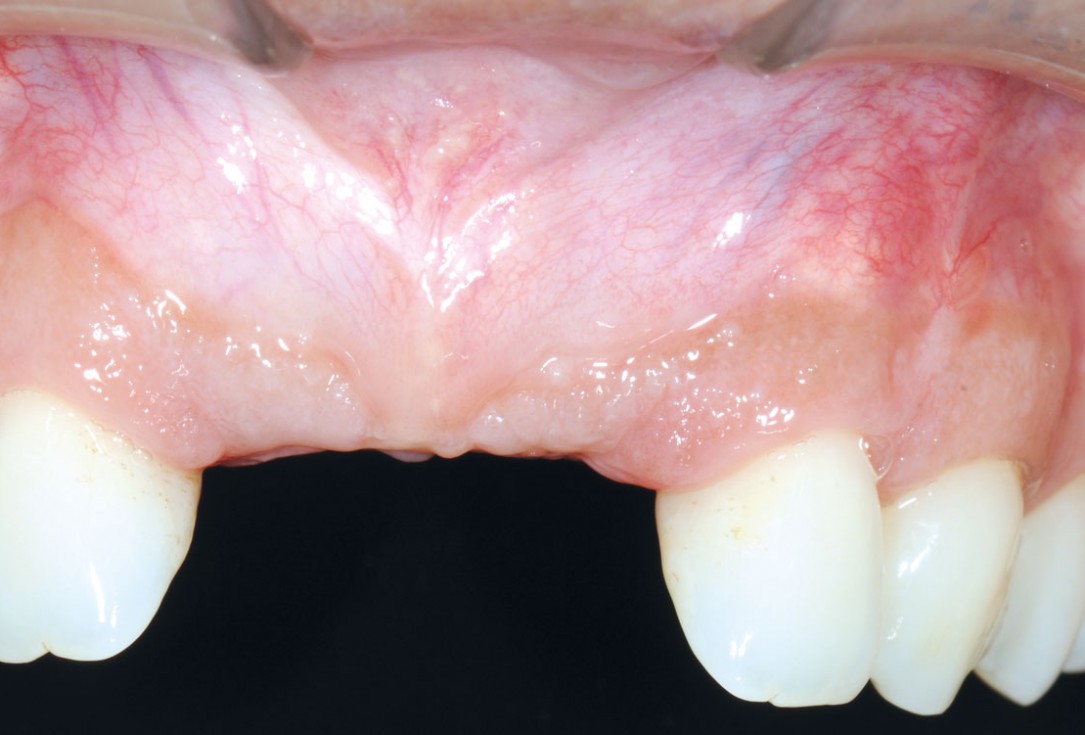

21/26 - 6 months after surgery: healthy soft tissuesBone augmentation in aesthetic zone with maxgraft® bonering - Dr. A. Patel